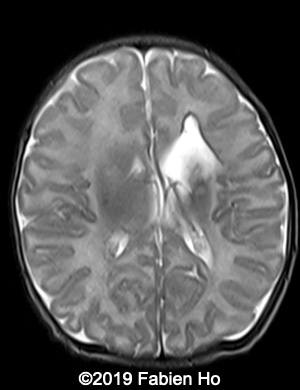

Images 1-3: in the left frontal lobe, hyperechoic with hypoechoic center lesion within the deep and periventricular white matter. Interestingly, this lesion has no mass effect on the lateral ventricle, and it has smooth margins.

Images 4-11, fetal brain MRI at 28 weeks: the left frontal lesion hence shows DWI hyperintensity, with T2* and T1 peripheral hyperintensity: ischemia with peripheral subacute hemorrhage. Note also that there is an associated blood clot in the left lateral ventricle. There is no obvious mass effect, nor peripheral edema. All these findin>gs are very suggestive of a clastic lesion.

Axial T2w

4

5